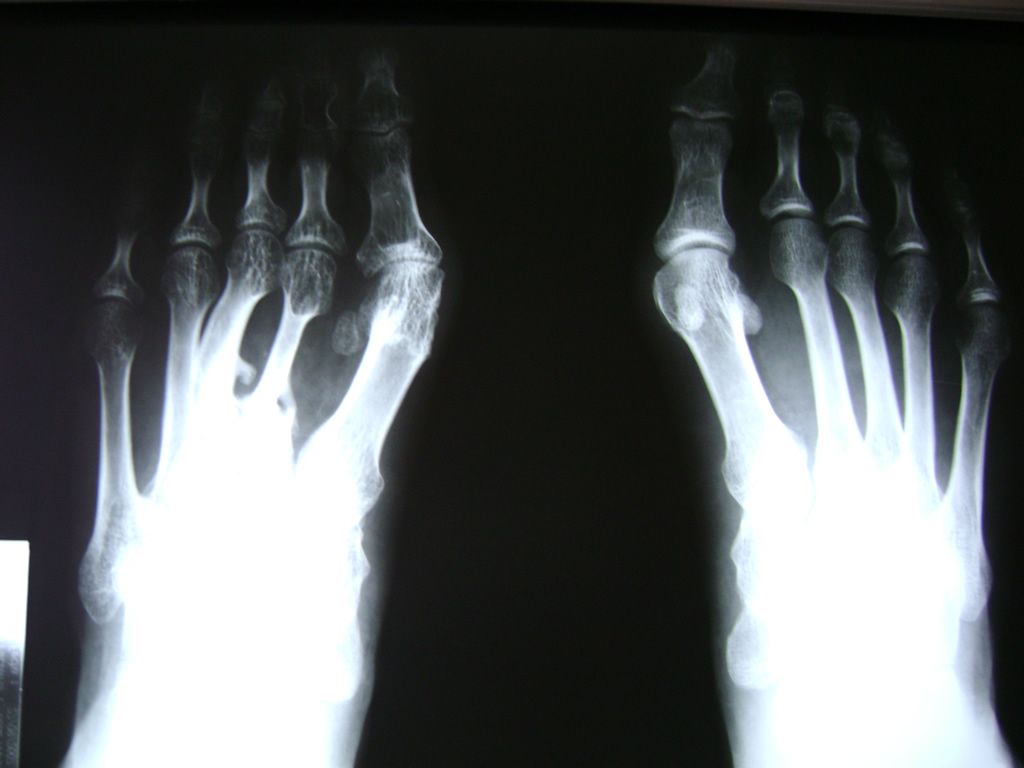

Las deformidades de los pies heredadas o adquiridas son el objeto principal de la cirugía reconstructiva del pie; sobretodo cuando producen dolor con el apoyo debido a una sobrecarga localizada o bien al no ser capaces de adaptarse a un calzado apropiado.

El pie consta de numerosas articulaciones con un mínimo movimiento cuya finalidad es adaptarse al terreno en cualquier situación. Cuando estas articulaciones que soportan grandes cargas y realizan movimientos sutiles se deterioran o funcionan de manera inapropiada, se suelen fusionar con el fin de evitar el dolor o bien restablecer la forma natural del pie y del apoyo.

Los síndromes de compresión nerviosa y tendinosa también son responsables de un gran número de enfermedades que requieren una intervención quirúrgica.